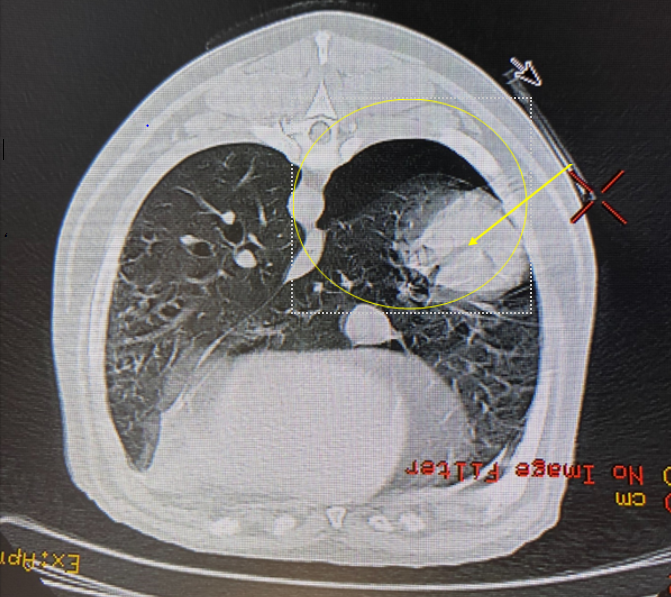

The patient was repositioned in sternal recumbency with the forelimbs extended cranially, therefore ensuring easy access to the area where the mass was located. It was possible to continue in the same examination package, so we repeated the scouts to ensure the patient was completely straight and the scanner could modulate correctly to the new patient position. The measuring tool was then employed, to measure how long the needle had to be to reach the center of the mass, and to accurately assess the required needle angle using axial, sagittal and coronal reconstructions. The distance from skin to centre of lesion was approximately 8cm (Image 7). A length of tape, marked every 1cm by small hypodermic needles, was placed over the right thorax from cranial to caudal. A scan was performed, and this allowed accurate identification of the location for biopsy needle placement (Image 8). Although this can cause artefacts, the mass could still be identified by adjusting WW and WL. The measurement tool can also be used to measure the distance from the spinous processes for more accurate location of the target area.

Image 7: Image showing the measurement of distance from the skin to the centre of the mass (yellow arrow).